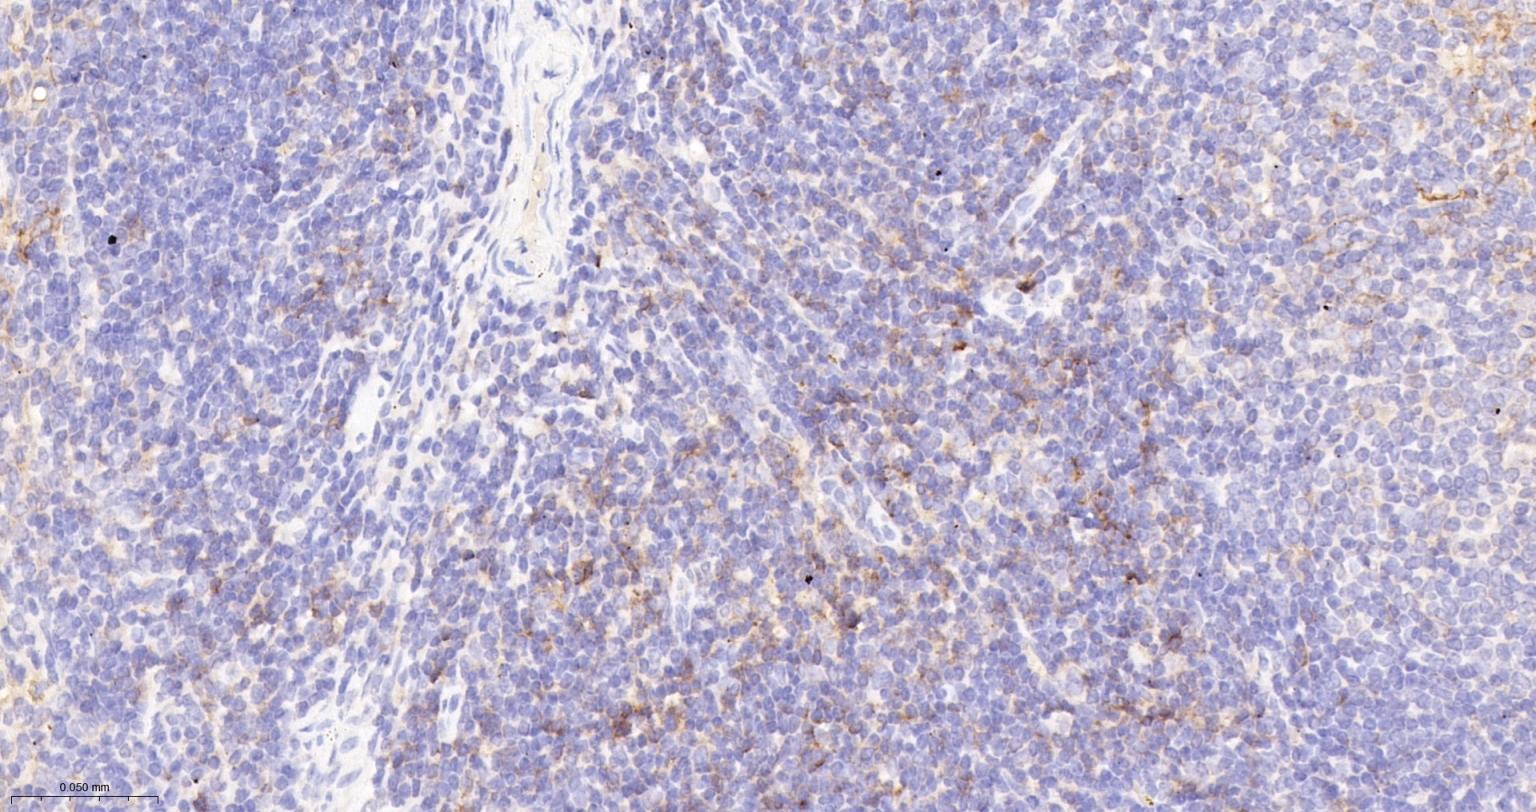

Paraformaldehyde-fixed, paraffin embedded Mouse Lymph; Antigen retrieval by boiling in sodium citrate buffer (pH6.0) for 15 min; The section was incubated with CD86 Monoclonal Antibody, Unconjugated (bsm-55596R) at 1:200 overnight at 4°C, followed by conjugation to the bs-0295G-HRP and DAB (C-0010) staining.

Paraformaldehyde-fixed, paraffin embedded Mouse Spleen; Antigen retrieval by boiling in sodium citrate buffer (pH6.0) for 15 min; The section was incubated with CD86 Monoclonal Antibody, Unconjugated (bsm-55596R) at 1:200 overnight at 4°C, followed by conjugation to the bs-0295G-HRP and DAB (C-0010) staining.